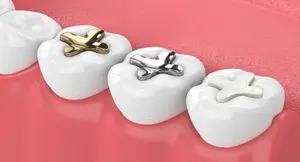

Fillings

Repair cavities and minor tooth damage to restore strength and function.